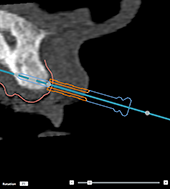

Anchor

pins and radiographic guide (edentulous workflow)

When using a

radiographic guide, the sleeve must be connected to the radiographic guide

but must not protrude beyond its intaglio surface.

|

Correct |

|

Incorrect: the sleeve of the anchor

pin is not attached to the radiographic guide and will not be

attached to the template. |

|

Incorrect: the anchor pin sleeve

protrudes through the radiographic guide and the template will

not fit into the patient’s mouth. |